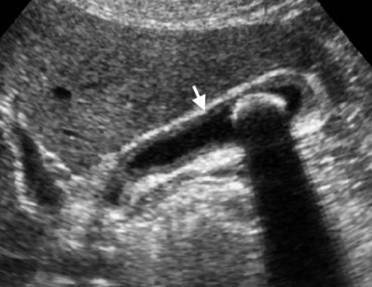

Adenomyomatosis

(Thickened gallbladder wall with comet tail artifact)